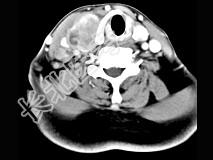

- 多项选择题女性,54岁, 右侧颈部肿大近1年,近来病人有声嘶、吞咽困难, CT扫描如图,请选择正确的描述和答案 ( )

A、右侧甲状腺肿大,密度减低

B、增强扫描示甲状腺呈不规则强化团块影,其内有低密度区,病灶境界不清

C、右侧颈内静脉增粗,其内可见不规则充盈缺损区

D、考虑甲状腺癌

E、右侧颈内静脉瘤栓形成